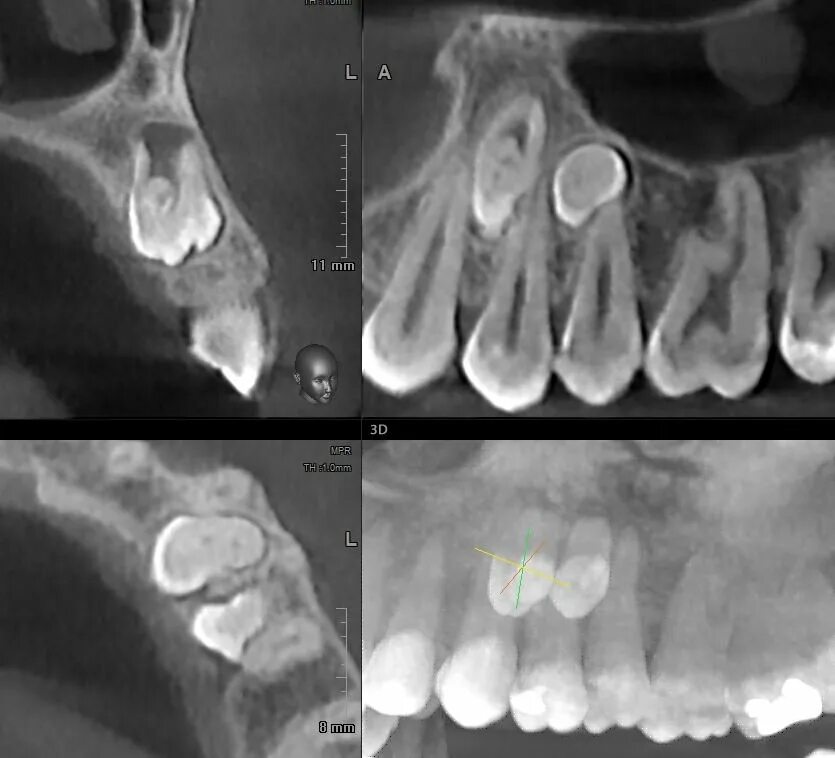

Picasso кт